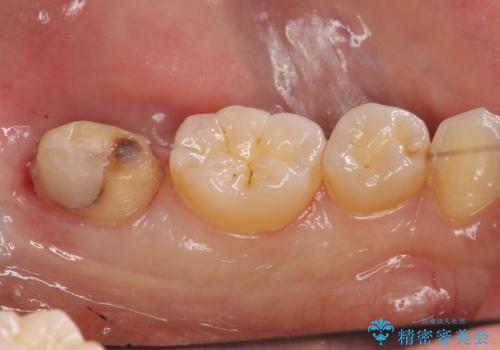

②歯周外科手術を行う。しっかり歯ぐきを下げ、マージンが歯肉縁下深くならないようにする

:虫歯も取り切って、きわがあったものが入るため①のようなことは起こりにくい。しかし外科処置が必要。

1:つめてあったセメントを除去、虫歯除去、セメントを再度つめる。処置後神経に問題がなければ手術の予約を取る。

2:歯周外科手術を行う